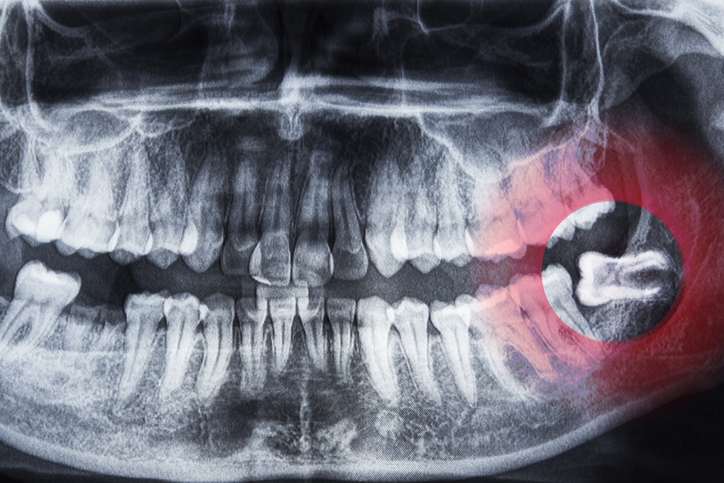

Through imaging, we can often see how a person’s wisdom teeth are developing before they erupt, catching any early signs that issues are likely to arise. The earlier we discover these problems the easier the procedure and recovery process are.

Wisdom teeth are the last teeth to come in, and many people’s mouths aren’t big enough to accommodate them. When a person’s wisdom teeth try to erupt in a crowded environment, you can experience issues ranging from impaction (stuck under the gum), to partial eruption, to eruption at an angle that puts pressure on nearby teeth and creates a difficult area to keep clean. Over time, this can even lead to cavities on the 2nd molars, which if the damage becomes severe enough, could require the 2nd molars to be extracted as well.

For some patients, there are signs that signal they could need an extraction, whether that’s pain, swelling, infection, or discomfort when chewing. For others, pain hasn’t become part of the equation yet, but imaging shows there could be problems down the line if the wisdom teeth continue to develop without intervention. Getting imaging early, and taking preventative measures before your wisdom teeth cause pain or infection is critical to avoiding complications.